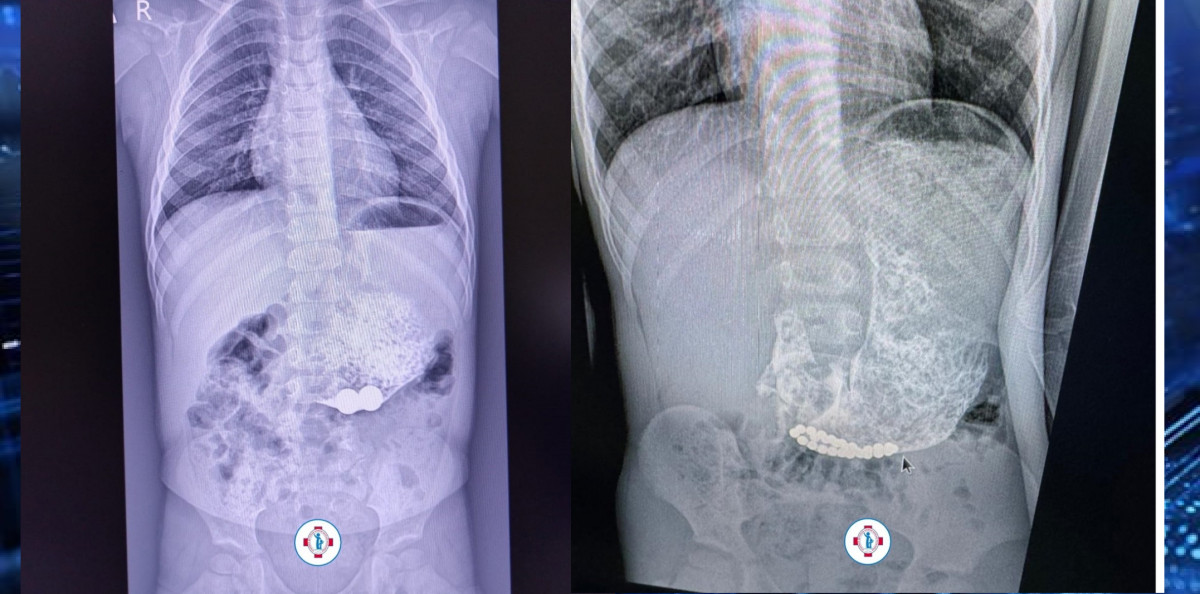

Магнитные шарики на рентгене: Интересные находки

Раздел: Картинки на заметку